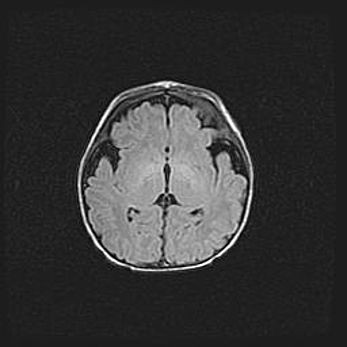

Неполная лизэнцефалия (пахигирия). Открытая гидроцефалия.

Возраст: 17 дней

Вес: 3110 г

Пол: мужской

Окружность головы: 33,5 см

Срок гестации: 35-36 недель

Лизэнцефалия—недоразвитие корковой пластинки и мозговых извилин в результате нарушения миграции нейронов коры. Поверхность мозговых полушарий гладкая. Микроскопически выявляется отсутствие нормальных слоев коры и скопление групп нейронов в подкорковом белом веществе.

Пахигирия—уменьшение числа вторичных извилин. В пораженном полушарии нервные клетки образуют толстый недифференцированный слой с неправильно расположенными нервными волокнами и группами гетеротопных клеток. Нервные клетки незрелые. Белое вещество истончено. При этом нередко аномально развит корково-спинномозговой путь.